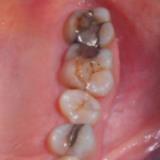

Immediate Implant Placement

A molar either maxillary or mandible always represents a little difficult and tricky scenario for implant placement immediately after extarction. There is always some sacrifice for the location, angle etc. however you save some time and patients go through a procedure once and it is a reliable method of replacing a tooth, when feasible. Dental implant is always a compromised replacement and a tooth restored with immediate placement is not any different.